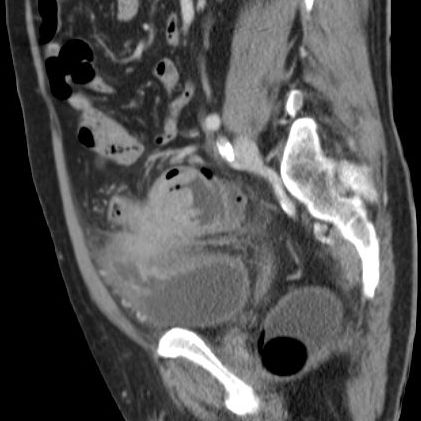

| Ileus | Das CT zeigt einen stenosierenden Sigmatumor mit ausgeprägtem Ileus. |